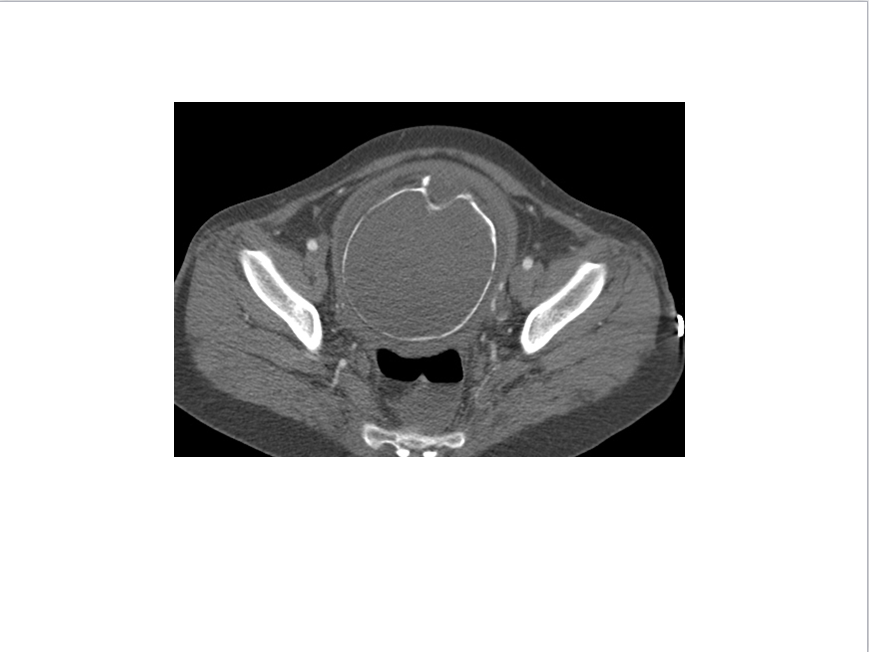

CT表现:自主动脉根部起至腹主动脉肾动脉水平可见撕裂之动脉内膜瓣影,子宫腔内可见胎儿影。

诊断结果:妊娠合并主动脉夹层(I型)。